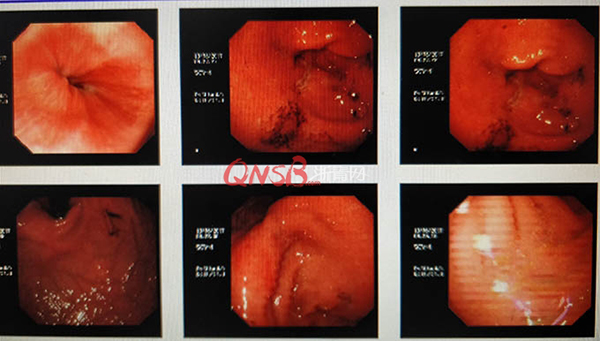

檢查結果出來后,小周大吃一驚,本以為自己的胃很健康,卻不想胃粘膜廣泛充血糜爛,長了兩個巨大的潰瘍(直徑大于2厘米),還有出血和咖啡色血痂。